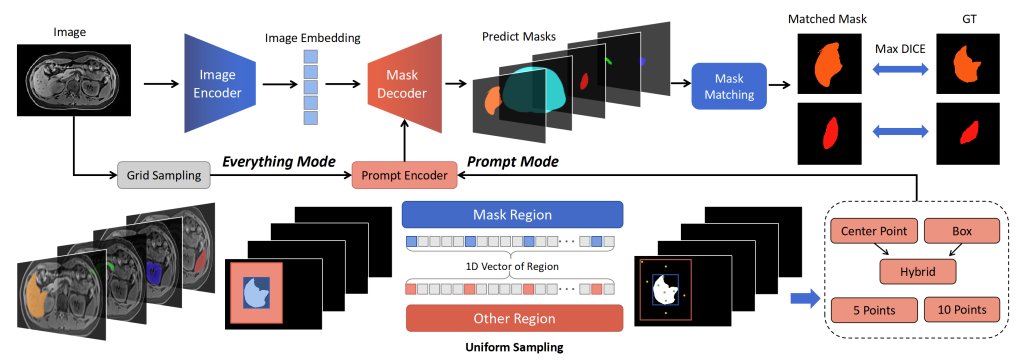

SAM提供不同类型的分割提示Prompt,包括点和方框等。

点的提示包括表示前景的正样本和表示背景的负样本点。

方框表示需要分割的物体的区域。

我们的测试策略包括Everything模式:自动分割 (S1H, S1B)以及Prompt模式:单个正样本点 (S2)、五个正样本点 (S3)、五个正样本点和五个负样本点 (S4)、单个方框 (S5)、单个方框和单个正样本点(S6),图3展示了我们设计的SAM测试框架。

图3 本研究设计的SAM详细测试框架。